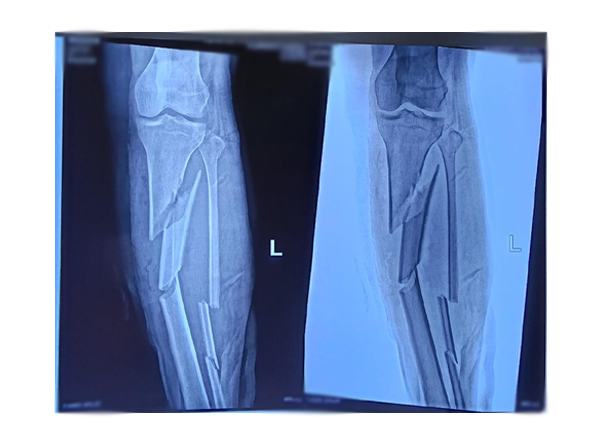

Orthopedic Surgery

Orthopedic surgery is a medical specialty concerned with the treatment